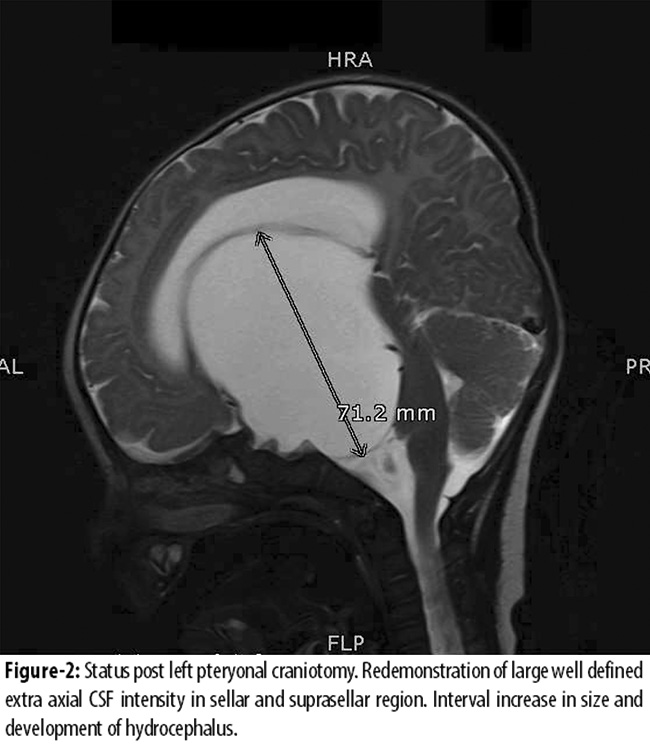

Since the bilateral frontal horns of the lateral ventricle were small, this cyst could not be accessed endoscopically via the right frontal horn. Therefore a left pteryonal craniotomy for cystocisternostomy of large suprasellar cyst was carried out on 08/04/15. The intra-operative findings included a cystic lesion containing CSF like fluid and involving sellar, suprasellar and left temporal area. The final diagnosis was of Suprasellar arachnoid cyst with raised ICP. Unfortunately, the success of the surgery was short lived and the baby presented in Neurosurgery Clinic after a month with bulging anterior fontanele and FOC of 43.5 cm (> 98th percentile). The repeat MRI showed hydrocephalus and recurrence of arachnoid cyst. Due to hydrocephalus left ventricle was dilated ten days later, Endoscopic Third Ventriculostomy with fenestration of cyst was done. On follow-up the baby is doing well with no delayed milestones and FOC at 90th percentile on the last visit. The parents\\\' consent was taken prior to surgery and the case to be available for any future research study as part of our institutions routine protocol.